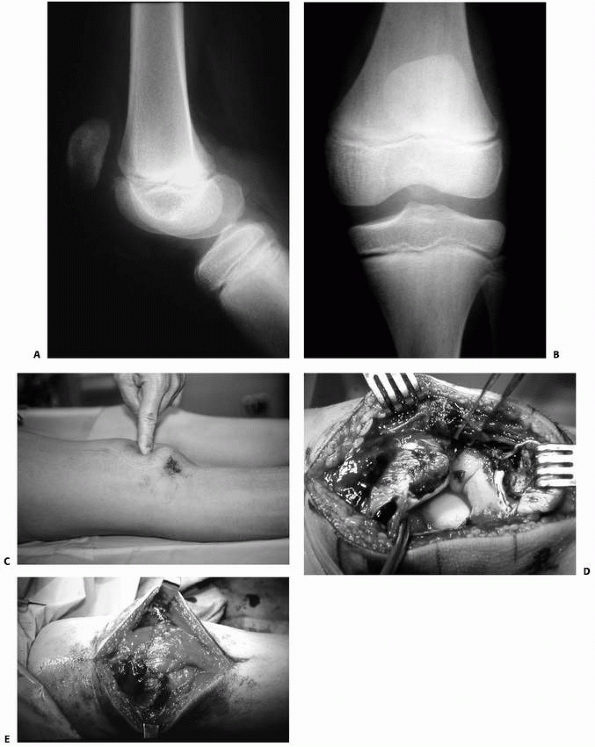

metaphysis may stretch and tear the tethered popliteal artery (Figs. 23-17 and 23-18).

![]() |

|

FIGURE 23-17

Posterior displacement of the epiphysis following fracture-separation at the time of injury can cause arterial injury. In addition, a posteriorly displaced fragment can cause persistent arterial occlusion by direct pressure. (Reprinted with permission from Skaggs DL, Flynn JF. Trauma about the knee, tibia, and foot. In Skaggs DL, Flynn JF, eds. Staying out of Trouble in Pediatric Orthopaedics. Philadelphia: Lippincott Williams & Wilkins; 2006.) |